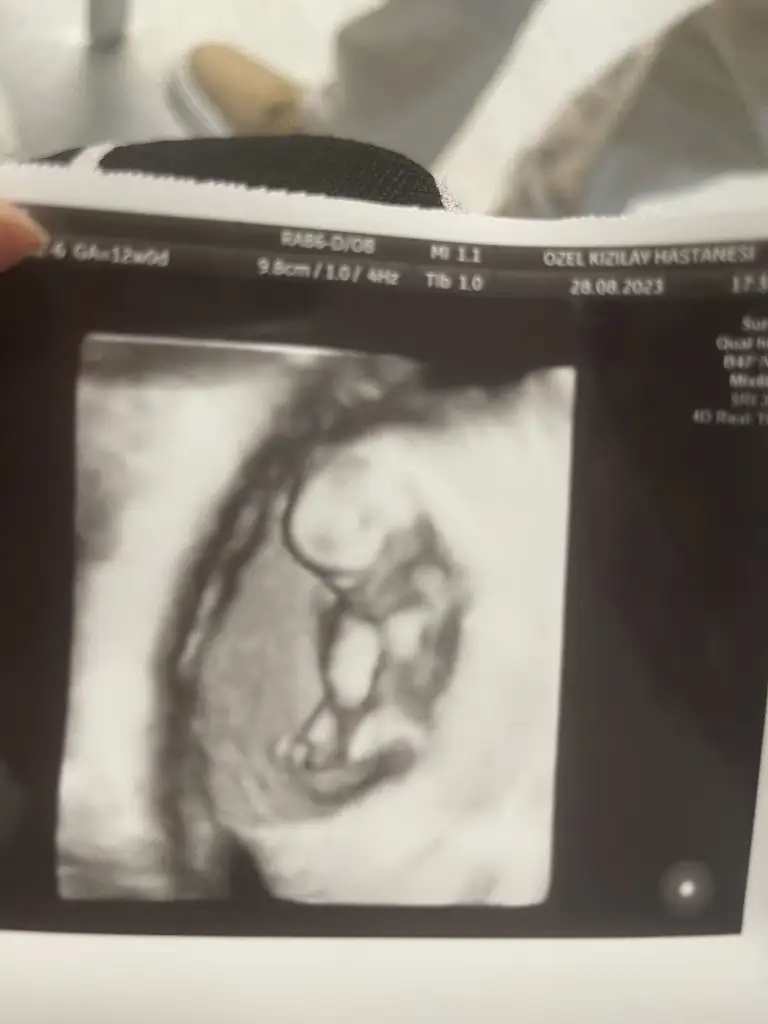

Selamlar kızlar . Dün kontrole bir hafta önceden gittim 12+1 im . Gripten dolayı korktum bebeğe bişey olmuştur diye . Doktor herşey normal dedi ama kalp atış sesi çok derinden ve çok hızlı geldi bana içime şüphe düştü . 170-180 gibiydi sanki . Size kalp atış sayısını söyledi mi doktorunuz ? Bi de hiç hareket etmedi nedense halbuki çikolata yiyip gittim . Foti koyuyorum cinsiyet tahmini yapabilecek var mı :)